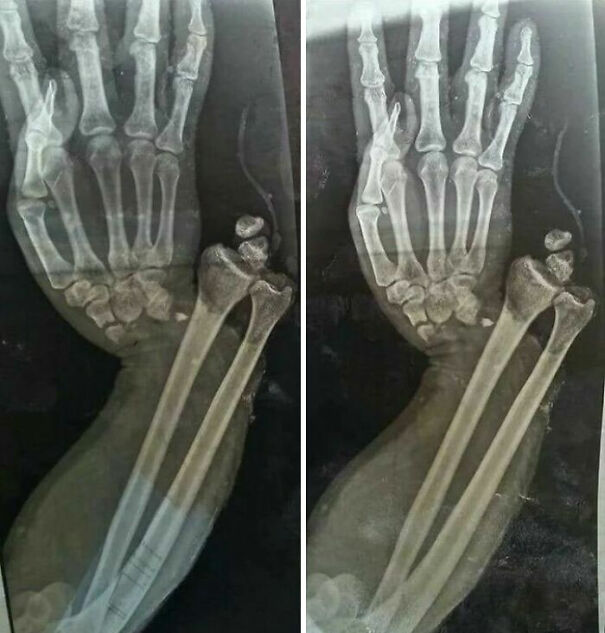

Open fracture dislocation of the wrist Source: www.instagram.com